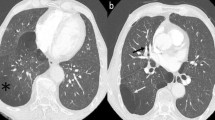

A 24 year old non-smoking caucasian lady presented with six months history of shortness of breath and productive cough, which did not improve with antibiotics. Clinical examination identified a bilateral significant wheeze. Routine haematological and biochemistry tests were normal. Her FEV1 was 1.6 l (55% predicted) and FVC 3.04 l (92% predicted). CT revealed an 8 cm well demarcated segment of consolidated lung in the left hilum (Figure 1). On PET scan (Figure 2) it was hypermetabolic returning an SUV max 4.8. The radiological appearance was suggestive of sequestration or hamartoma. A CT-guided biopsy was indeterminate and she was therefore referred for surgery. During VATS, the lesion was identified in the left hilum in a haemorrhagic capsule.

CT scanning reveals three morphologic patterns of unicentric thoracic Castleman’s disease: a solitary, noninvasive mass (50% of cases); a dominant mass with involvement of contiguous structures (40% of cases); or a matted lymphadenopathy confined to a single mediastinal compartment (10% of cases) [6]. Hypervascularity of the lesion may reveal homogeneously intense contrast enhancement in CT. 5–10% of Castleman's disease demonstrated intralesional calcifications, typically being discrete, coarse, or distinctive with an “arborizing” pattern in enhanced CT [6]. For thoracic Castleman's disease MRI can be used as it demonstrates the extent of the tumour, clarifies its relationship to the bronchovascular structures and shows the feeding vessels. Similar to other inflammatory disease, Castleman’s disease shows mild to moderate FDG uptake in PET scan. Histological diagnosis before surgical removal can be done by CT guided biopsy, EUS and EBUS if the anatomical position permits.